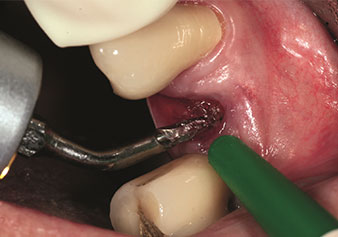

Gestione alveolare

Un’applicazione che viene spesso sottovalutata è l’estrazione atraumatica di radici di denti o frammenti di radici nell’ambito della gestione alveolare. I periotomi sottili, che sono attualmente disponibili in due versioni (EX1 ed EX2 di W&H), possono essere, inoltre, utilizzati per rimuovere con facilità denti che hanno precedentemente subito uno specifico trattamento endodontico o con radici anchilosate. Ne consegue l’estrazione di alveoli in cui i tessuti duro e molle sono entrambi completamente intatti in quanto è generalmente possibile evitare la riflessione.

Ciò pone le basi ottimali per un trattamento con impianto immediato o successivo (Figure 1 e 2 inserite grazie alla gentile concessione del Dott. Torsten Conrad, Bingen a. Rhein).

Foto: © Dott. Torsten Conrad (Bingen am Rhein)